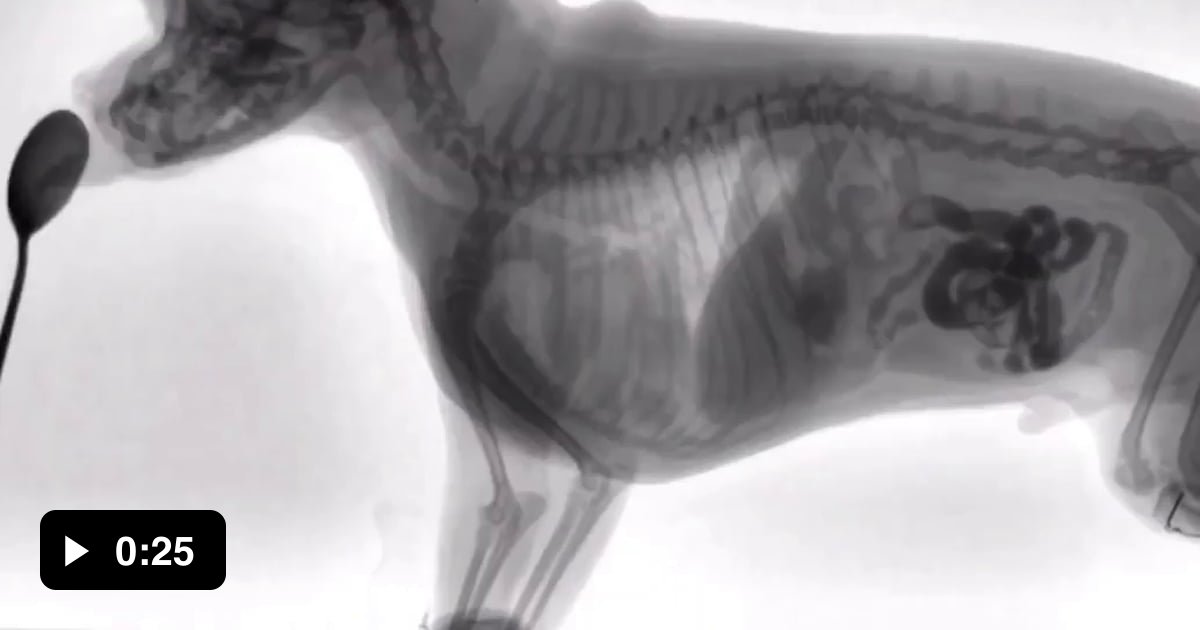

Veterinary Fluoroscopy of a dog eating food 9GAG Fluoroscopy Dog Cost Fluoroscopic examinations are a specialty service offered to pets at uvths. we use fluoroscopy to investigate specific problems such as: It is also used for investigating airway disease. A swallowing study looking at oesophageal motility disorders,. sydney veterinary emergency & specialists is home to some of the most sophisticated diagnostic imaging modalities in veterinary medicine. Evaluation of pharyngeal. Fluoroscopy Dog Cost.